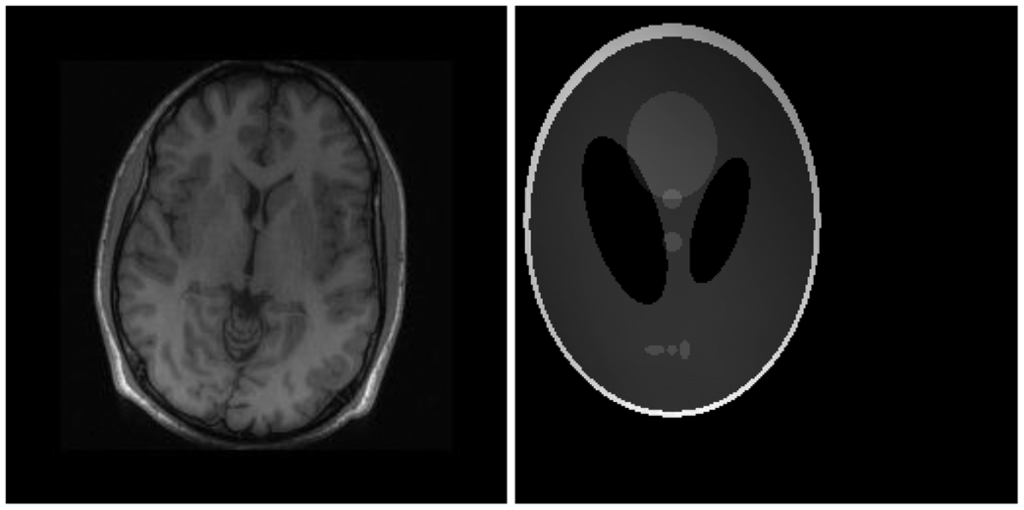

There are two sets of ground-truth data used for our experimental evaluation (Figure 7). The brain data and the Shepp-Logan phantom have been used previously in [4]. The brain data is a fully sampled T1 weighted scan of a healthy volunteer. The volunteer was scanned using Spoiled Gradient Echo sequence with the following parameters—echo time = 8 ms; repetition time = 17.6 ms; flip angle = 20 degrees. The scan was performed on a GE Sigma-Excite 1.5-T scanner, using an eight-channel receiver coil. The 8-channel data for Shepp-Logan phantom was simulated. The ground-truth is formed by sum-of-squares reconstruction of the multi-channel images.

For our non-convex formulation, we found that the best results were obtained for p = 0.5 (this value of p has also been suggested in [11]). The quantitative reconstruction results are shown in Table 1. Normalized Mean Squared Error (NMSE) is the metric used for evaluation. The best reconstruction (lowest error) results are shown in bold.

The DCS reconstruction yields the worse results. This is expected—DCS is an ad hoc algorithm and consequently it fails. Our proposed non-convex analysis prior formulation yields the best results. The synthesis prior formulation is slightly worse off than the analysis prior. The SAKE technique does not yield as good results as our proposed technique. CS SENSE and l1SPIRiT yield better results than SAKE, but they have to be thoroughly calibrated and hence are not robust.

Although NMSE is an often used metric for evaluating the reconstruction accuracy, it does not always reflect the qualitative aspects of reconstruction. For qualitative evaluation we show the reconstructed images in Figure 9. Owing to limitations in space we only show the results for variable density random sampling. The qualitative results more or less corroborate the quantitative results. With 6-fold undersampling, all the methods apart from our proposed analysis prior formulation yields significant reconstruction artifacts.